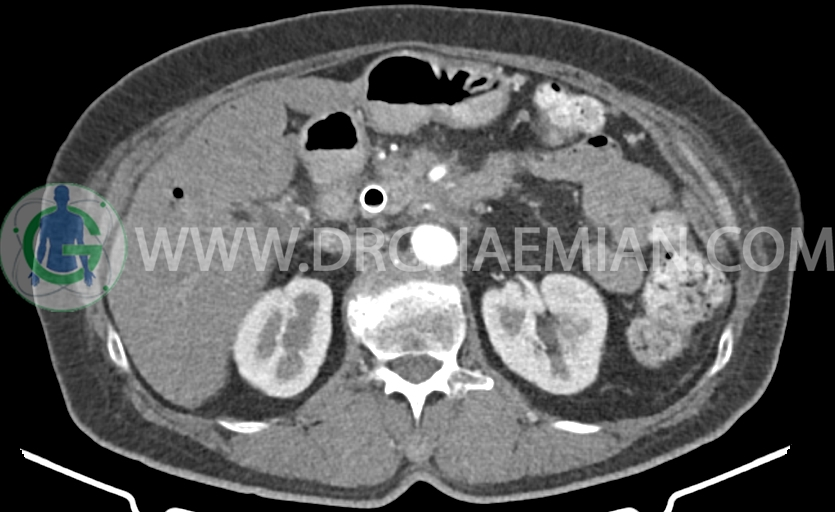

در سی تی اسکن اسپیرال شکم و لگن با و بدون کنتراست خوراکی و وریدی- پروتکل پانکراس (مولتی دیدکتور 16 با مقاطع ظریف و بازسازی های ساژیتال و کرونال) :

– Fullness در سیستم پیلوکالیسیل کلیه ها (بیشتر سمت چپ) احتمالاً فاقد اهمیت بالینی است و نسبت به سی تی اسکن قبلی بهبود نشان می دهد.

–پرومیننسی عروق لگنی، بدون تغییر نسبت به سی تی اسکن قبلی) (?Pelvic congestion syndrome )

-مایع آسیت اندک در حفره لگن (کاهش نسبت به سی تی اسکن قبلی)

-کلسیفیکاسیون جدار آئورت و ایلیاک